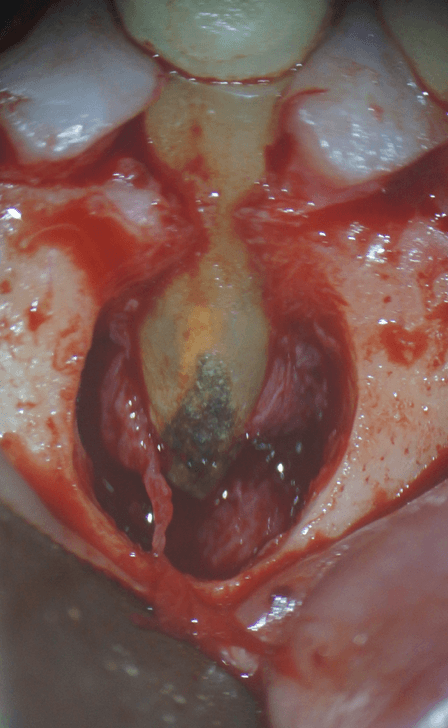

歯茎の裏側を見ると、こんなに骨が溶けています。根の先の炎症は恐ろしいですね。根の表面を確認すると、黒い石のようなものがへばりついています。これは、歯石です。これが、今回の症状の原因です。

マイクロスコープを用いて、処置を行います。まずは、根の先をカットします。と、同時に歯石も取り除きます。

そして、その他に汚れの取り残しがないか、確認します。

取り残した汚れがないことを確認したら、今度は、根の先から、薬をつめるための器作りを行います。

その器の中に、MTAセメントと呼ばれる材料を入れます。

この後、歯茎を縫い、終了です。